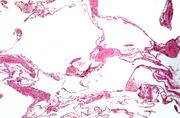

| 14:54, 20 August 2013 | IPLab5Hemochromatosis6.jpg (file) | 99 KB | This trichrome stain of liver section demonstrates the increased fibrous connective tissue in this liver. Note that the liver nodules (1) are surrounded by fibrous connective tissue (2). | 1 | |